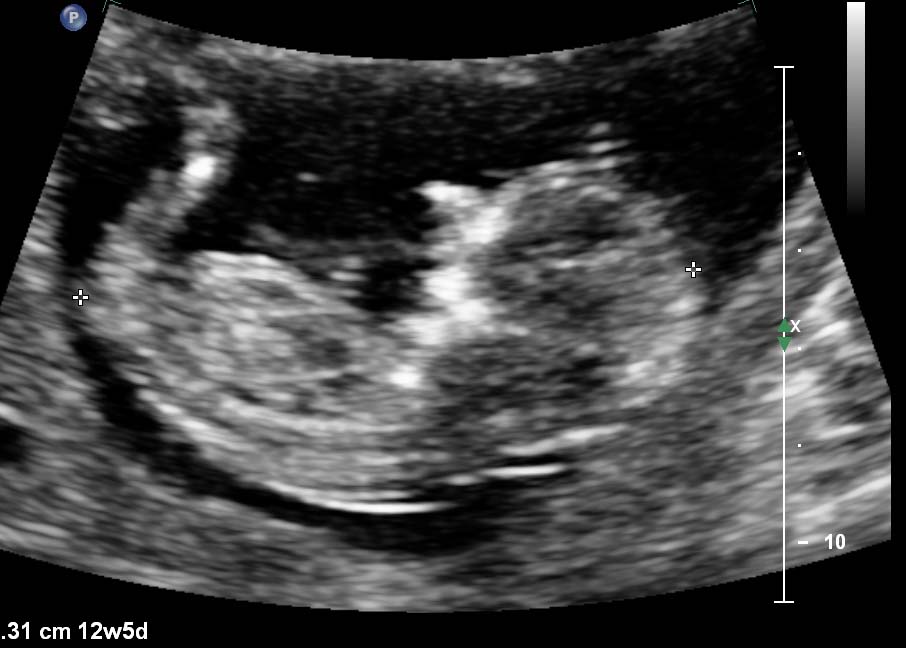

I am as curious as everyone else is with their beautiful scans. I have done a somewhat lazy sway after a miscarriage in October last year. I am of course over the moon with making it this far, but would love to know your guesses....PLEASE:):flowerz:Attachment 9063Attachment 9064